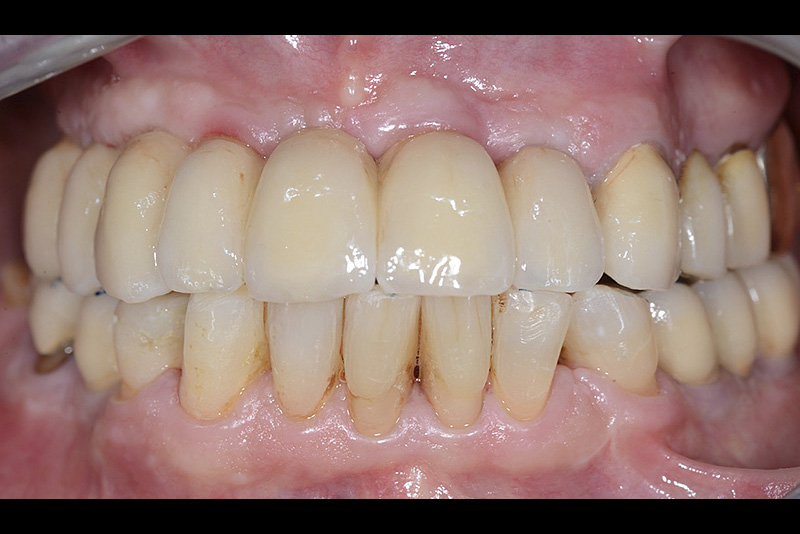

PREMESSA: in seguito all’estrazione dell’incisivo laterale superiore di destra, resasi necessaria per cause batteriche, si decide di affrontare il caso con il posizionamento di un impianto in sostituzione dell’elemento mancante dopo guarigione del sito infetto. Con tecniche rigenerative sia dei tessuti ossei mancanti a causa dell’infezione pregressa, sia dei tessuti gengivali che appaiono inizialmente troppo spostati in alto, si ripristina una corretta morfologia delle parabole (contorni) gengivali e delle papille interdentali (triangoli di gengiva tra due denti vicini).

Vengono utilizzati 2 tipi di provvisori: il primo, cementato ai denti vicini, viene utilizzato dal momento dell’estrazione del dente fino ad impianto osteointegrato (circa 6 mesi); il secondo, avvitato direttamente all’impianto, ha una funzione di prova estetica ma soprattutto di guida per la maturazione dei tessuti gengivali peri-implantari portandoli verso la maturazione completa prima di posizionare la corona finale in disilicato di litio.